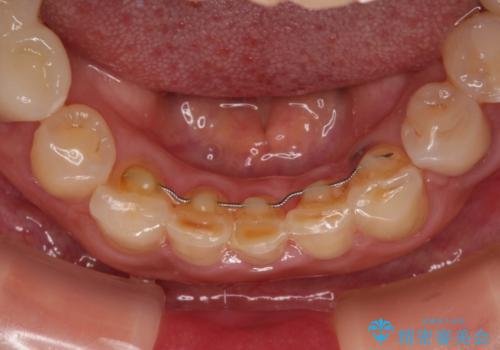

- 割れていると言われて放置してしまった歯や、前歯のデコボコなどが気になるとのことで来院された患者様です。

左上の歯は割れてしまっており、抜歯のうえインプラント治療が必要であり、他にも抜歯の必要な歯がある状態でした。

上顎はほぼ全ての歯をセラミッククラウンにて補綴治療を行う必要があるため、気になるデコボコや深い咬み合わせを改善するために下顎と上顎の臼歯部の矯正治療を行うこととしました。

並行して左下にはインプラントを埋入し、矯正治療を終えると同時に補綴治療を行うこととしました。